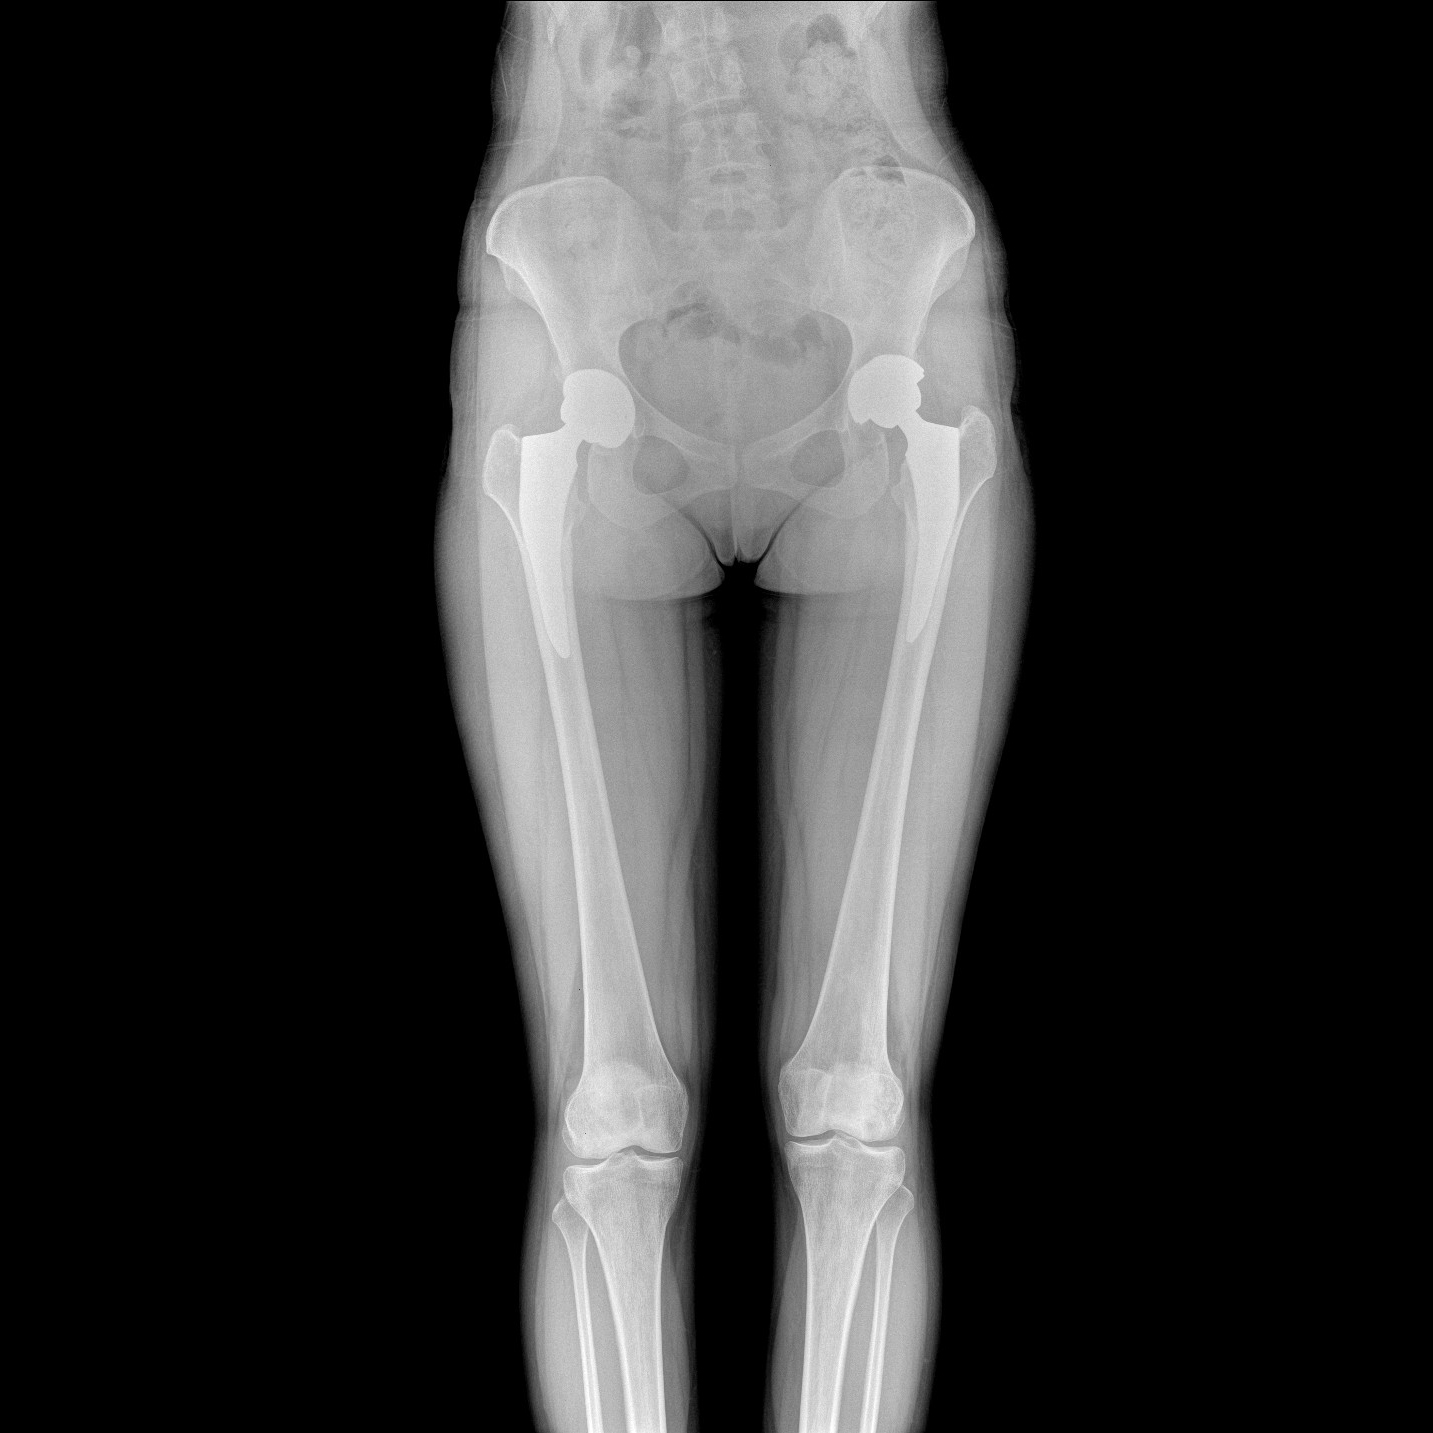

支持全脊柱摄影、双下肢摄影、脊髓造影、复杂创伤、人工关节置换、关节损伤的修复重建等大视野临床应用

全脊柱一次成像 不拼接

17"*34"有效视野,一次成像不拼接。相较于多张摄影再软件拼接的DR设备,PLX8600解决了拼接图像存在密度不均匀,拼接处图像配准和放大效应等问题,给临床带来了大视野影像解决方案,可一次性覆盖全脊柱或双下肢影像。

Clinical picture

临床图片